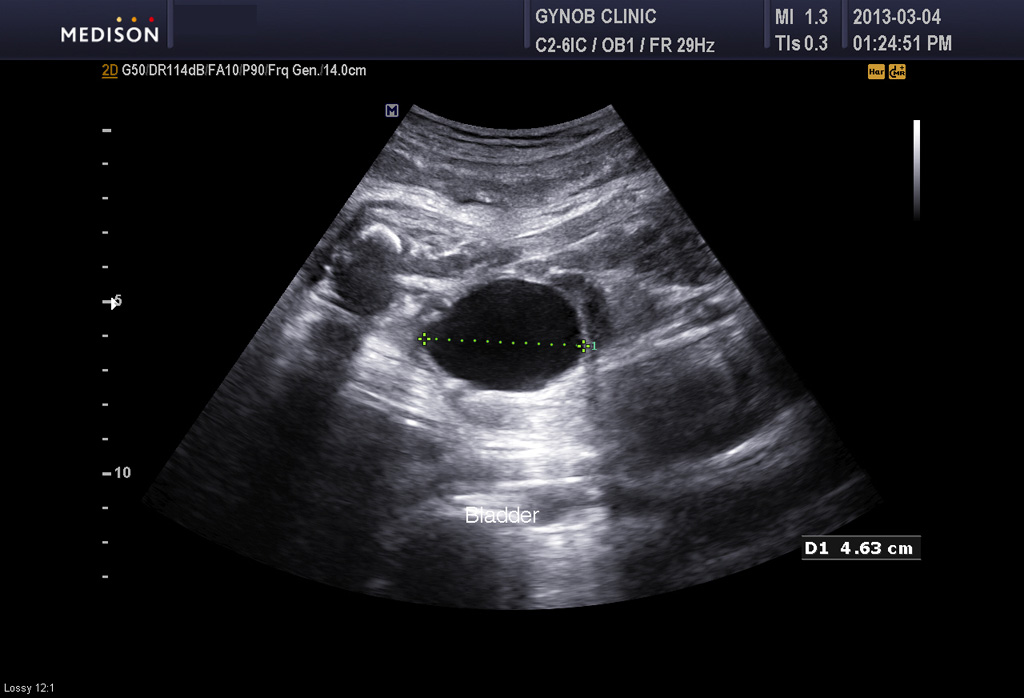

그런데 그 산모는 초음파 검사상 태아의 방광이 수시간 동안이나 비워지지 않고 꽉 찬 상태로 보여 혹시 태아의 비뇨기 계통의 기형인 "요관 말단 판막 (posterior urethral valve)"이라고 하는 기형이 있지 않은가 하는 의심이 들었습니다.

요관 말단 판막은 그리 흔한 기형은 아니지만 남자 아기에게서 주로 생기고 방광의 소변이 원활하게 체외로 나오지 못하는 기형입니다.

따라서 그런 기형이 있을 경우 방광은 많이 커지고 양수는 줄어들게 됩니다.

아래 사진은 그 산모분의 산전 진찰시 초음파 사진인데 위는 양소 과소증을 나타내 주는 사진이고 아래는 태아 방광의 사진입니다.